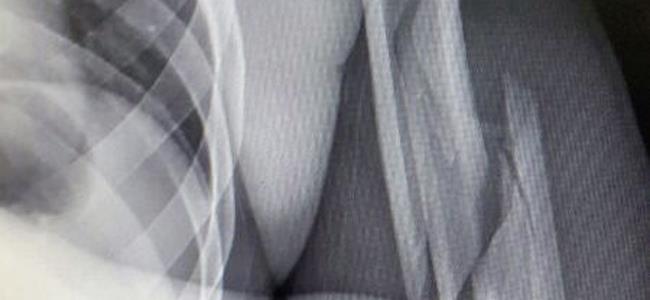

خضع نجم فريق الحكمة ومنتخب لبنان لكرة السلة ايلي رستم صباح الاربعاء 4 حزيران لجراحة دقيقة في كتفه اليسرى في مستشفى المركز الطبي الجامعي LAU (مستشفى رزق) في الاشرفية، على يد الدكتورين الجراحين الفرد خوري ووسام بويري استمرت ثلاث ساعات، وانتهت بنجاح كبير. وتعتبر إصابة رستم صعبة وهي كناية عن كسر مثلث في الـ HUMERUS أي المنطقة بين الزند والكتف الايسر، وهو سيغيب عن الملاعب بين ثلاثة واربعة أشهر، بحسب ما أوضح معالج الفريق الفيزيائي الدكتور خليل نصار لموقع "ملاعب" وتلقى رستم مساء الاربعاء اتصالاً من ولي الحكمة المطران بولس مطر الذي اطمأن الى صحته وتمنى له الشفاء العاجل، كما زاره في المستشفى رئيس النادي نديم حكيم وعدد من اعضاء اللجنة الإدارية للنادي. وشكرت إدارة الحكمة للدكتورين خوري وبويري عنايتهما باللاعب النجم. وينفرد موقع "ملاعب" بنشر صور الاشعة للاعب النجم مع التمني له بالشفاء العاجل.